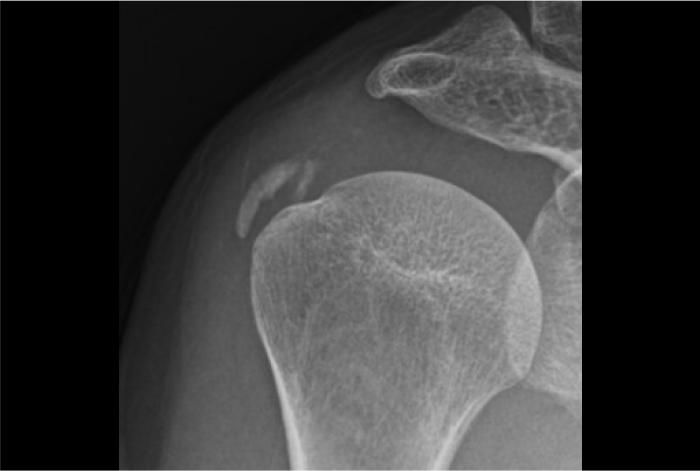

어깨에 특별한 충격이나 외상이 없었는데도

계속해서 통증이 느껴지시나요?

수면 도중 깰 정도의 통증을 느끼시나요?

어깨를 감싸고 있는 회전근개 힘줄에 칼슘

성분이 침착되면서 염증을 일으키는 질환입니다.

석회가 자리를 잡으면 자연흡수가 어렵기 때문에 조기 진단과 치료가 매우 중요합니다.